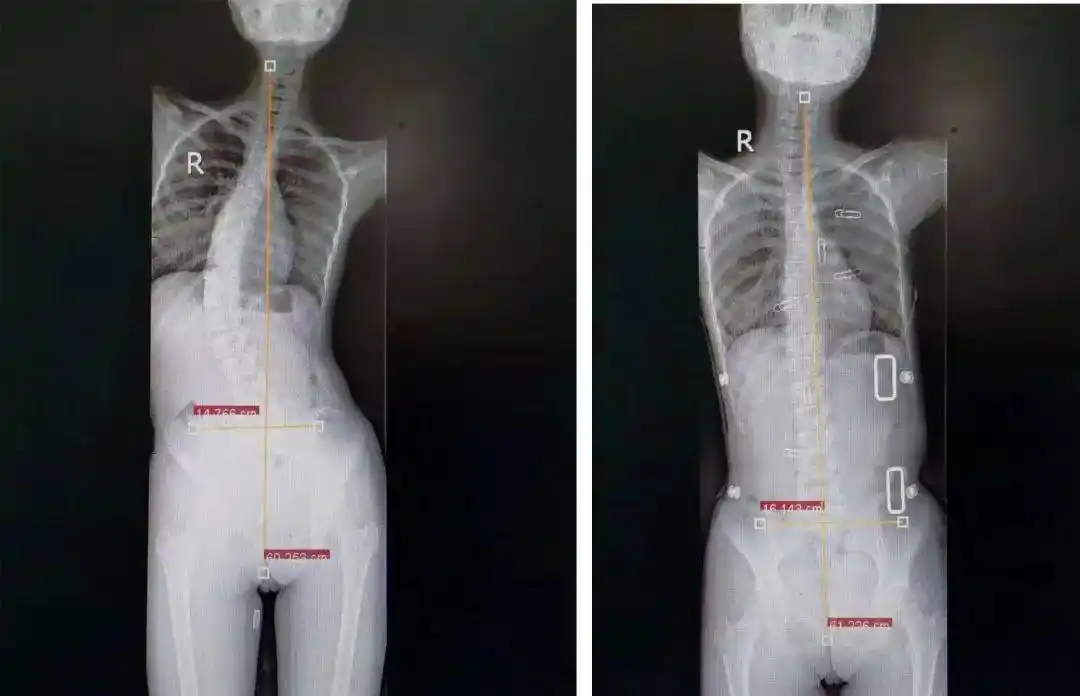

先天性脊柱侧弯矫形术,女,14岁 - 好大夫在线